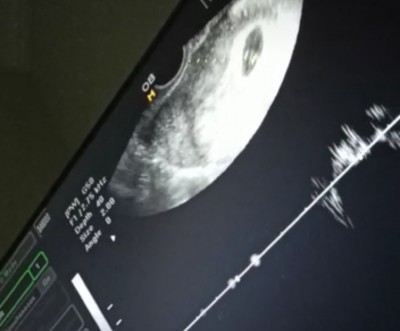

Merhaba güzel anneler hayırlı akşamlar Benim bi sorum olucaktı sizlere bu benim bebeğimin 5 +4 ultrason görüntüsü görüntüde bi emyriyo yok henüz

bu normalmi sizlerin nasıldı

benim 6 haftada böyleydi ve kalp atışı vardi. Biraz daha bekleyin bence